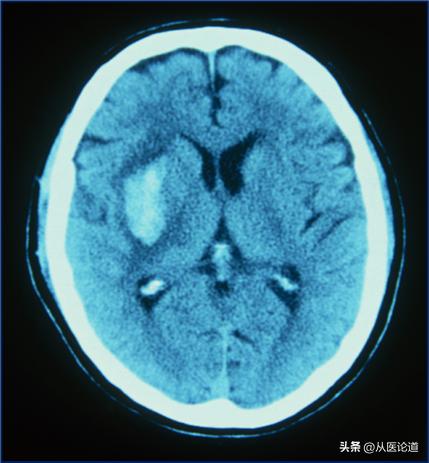

内脏出血:呕血、黑便、咯血、尿血、阴道出血、颅内出血危及生命。

1、重症ITP患者(PLT <10×109/L)发生胃肠道、泌尿生殖道、中枢神经系统或其他部位的活动性出血或需要急诊手术时,应迅速提高血小板计数至50×109/L以上。